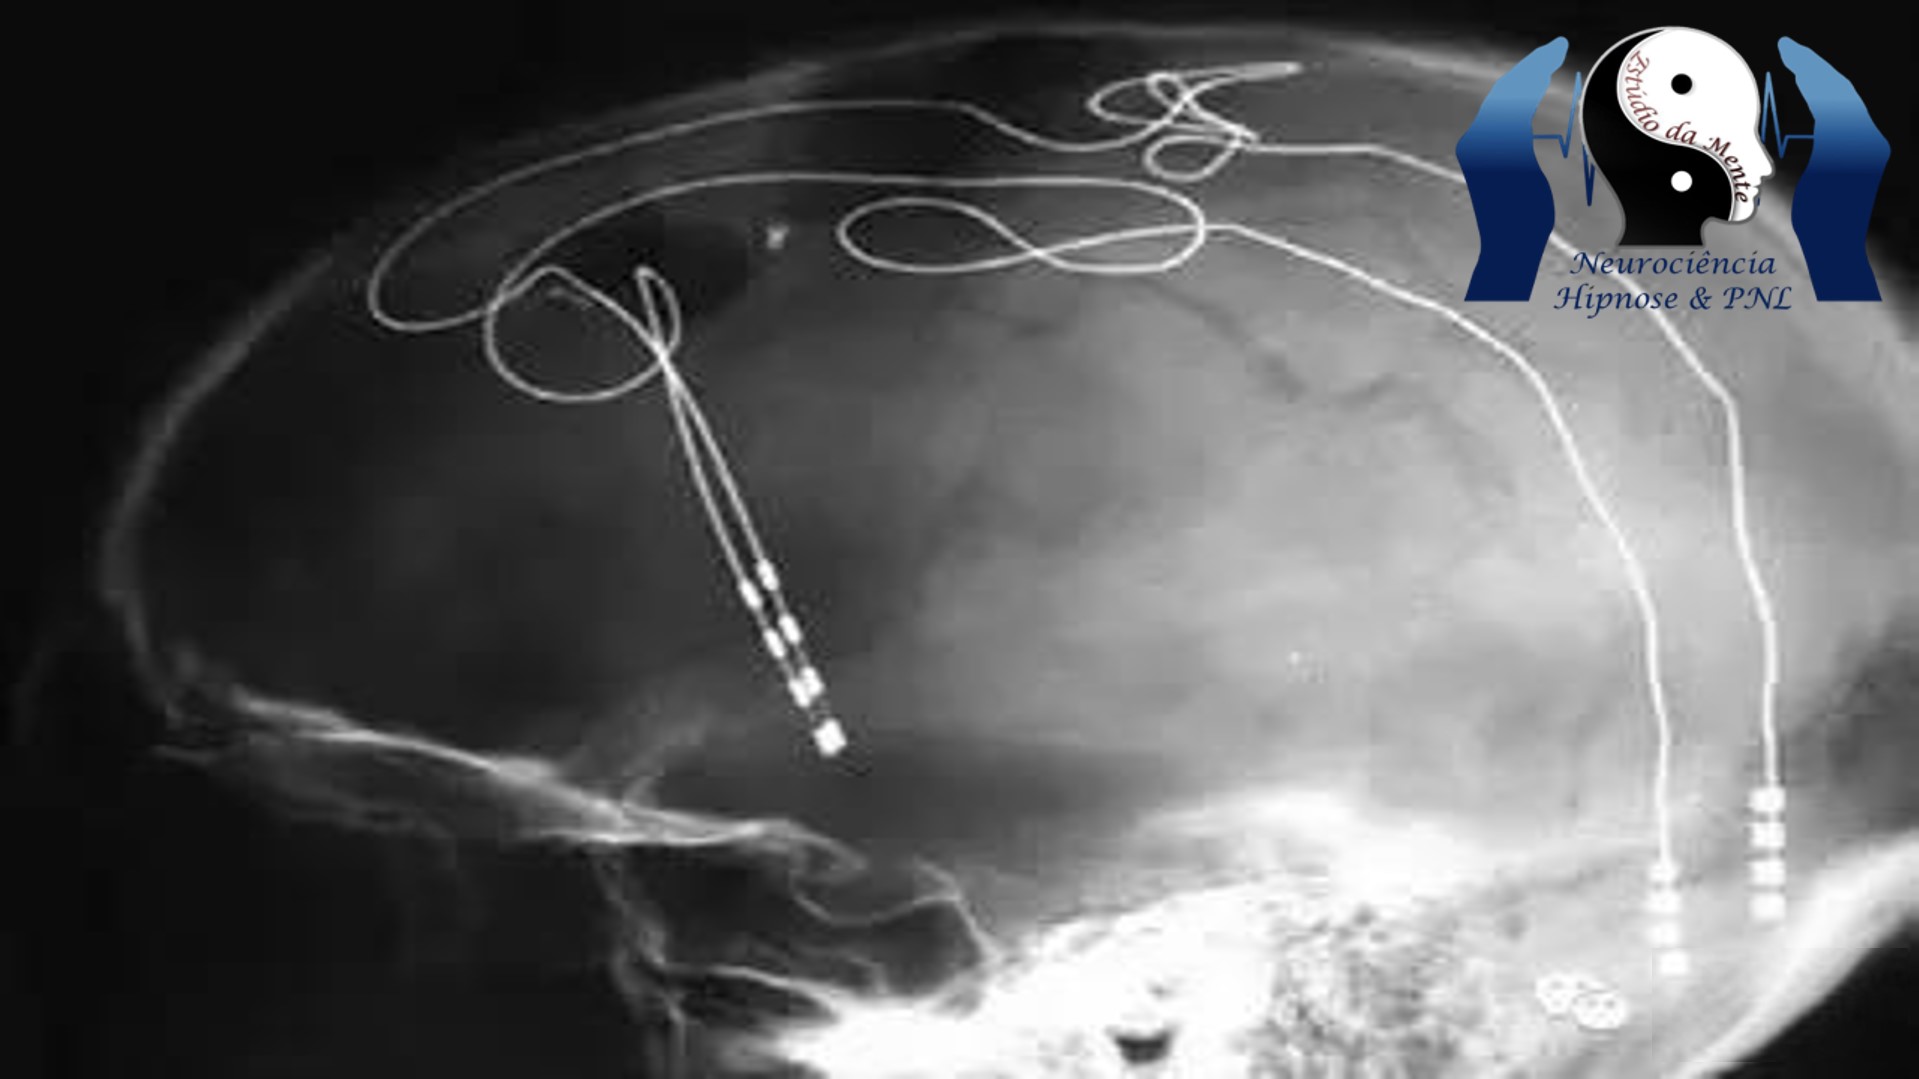

A estimulação cerebral profunda, atualmente aprovada pela Food and Drug Administration dos EUA para tratar tremor essencial, doença de Parkinson, epilepsia e transtorno obsessivo-compulsivo, é um procedimento neurocirúrgico que envolve a colocação de um neuroestimulador (às vezes chamado de “marcapasso cerebral”) , que envia impulsos elétricos de alta frequência através de eletrodos implantados no fundo do cérebro para áreas específicas do cérebro responsáveis pelos sintomas de cada distúrbio.

Especificamente, o estudo documenta os dados de resultados a longo prazo (4 a 8 anos) de 28 pacientes que foram incluídos em um ensaio clínico de rótulo aberto do SCC DBS para depressão resistente ao tratamento. Três quartos de todos os participantes preencheram o critério de resposta ao tratamento para mais da metade de sua participação no estudo. Dos 28 participantes, 14 completaram pelo menos oito anos de acompanhamento, 11 outros completaram pelo menos quatro anos e três desistiram antes de oito anos de participação. Os dados apresentados neste estudo apóiam a segurança a longo prazo e a eficácia sustentada do SCC DBS na depressão resistente ao tratamento.